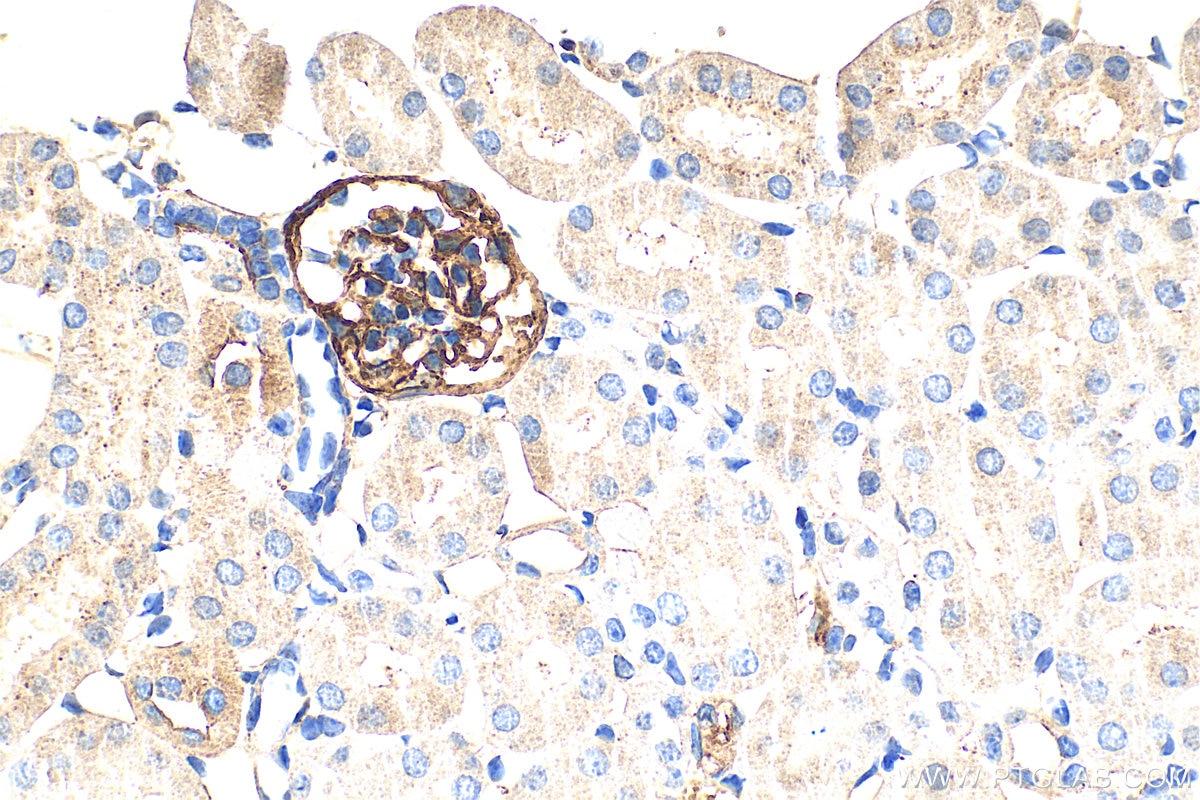

| Positive IHC detected in | mouse lung tissue, mouse kidney tissue Note: suggested antigen retrieval with TE buffer pH 9.0; (*) Alternatively, antigen retrieval may be performed with citrate buffer pH 6.0 |

33099-1-AP targets Podoplanin in WB, IHC, ELISA applications and shows reactivity with mouse samples.

Podoplanin was identified as a glycoprotein found in the cell membranes of glomerular epithelial cells (podocyte) (PMID: 9327748). It is a lymphatic marker because the expression of podoplanin has been detected in lymphatic but not blood vascular endothelium, and is useful as the marker of tumor-associated Lymphangiogenesis. Podoplanin has a function in developing testis, most likely at the level of cell-cell interactions among pre-meiotic germ cells and immature Sertoli cells. It may be involved in cell migration and/or actin cytoskeleton organization. When expressed in keratinocytes, PDPN induces changes in cell morphology with transfected cells showing an elongated shape, numerous membrane protrusions, major reorganization of the actin cytoskeleton, increased motility and decreased cell adhesion. It is required for normal lung cell proliferation and alveolus formation at birth. PDPN induces platelet aggregation. It does not have any effect on folic acid or amino acid transport and does not function as a water channel or as a regulator of aquaporin-type water channels.